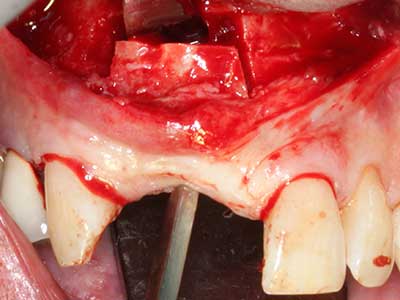

Autologous bone transplants are used in the form of blocks, shells, rings and are also combined with bone replacement materials as chips. If the implant site is prepared at the same time as the augmentation, various bone filter systems have proven effective for collecting the resulting bone chips. As an alternative, the implant site can be prepared using a low-speed device without irrigation. If an implant is not inserted, bone chips can be harvested from the periphery with bone scrapers. This is also possible with piezosurgery using specialized attachments that yield higher-quality bone chips compared chips harvested with round drills, as has been confirmed in a study comparing the two methods (Chiriac, Herten et al. 2005).

Piezosurgery has additional advantages when harvesting bone blocks. In addition to the high precision with osteotomy described above, the use of the thin saw tips specifically minimizes loss of material. Greater loss of material during harvesting can be expected with the thicker instrument tips, particularly when using Lindemann drills (Lakshmiganthan, Gokulanathan et al. 2012). The basal separation, which is necessary particularly for retromolar block transplants, is simplified by specially designed rectangular saws, with the result that piezosurgery is viewed as a precise, simple and safe procedure for harvesting retromolar bone blocks (Happe 2007) (Fig. 1-12).